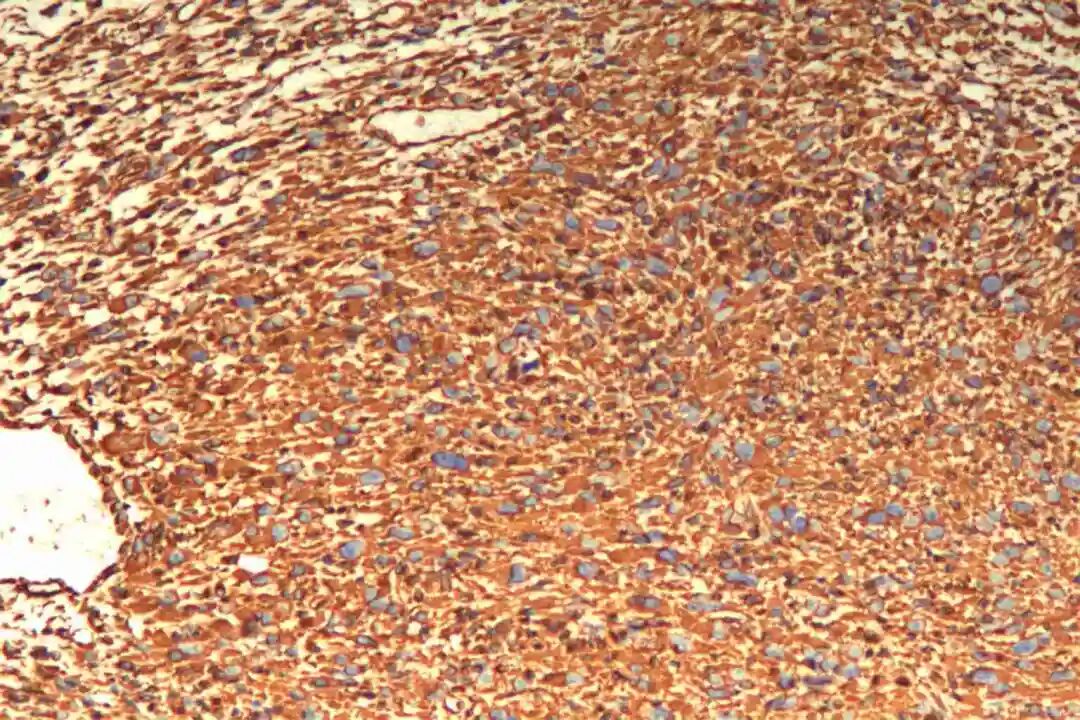

免疫组化:Vimentin(+),CKpan(-),SMA(+),Desmin(-),CD34(-),S-100(-),BCL-2(+),CD68(部分+),Ki67(40%+)。

3、免疫组化

必标套餐:SMA(+)、desmin(+)、h-caldesmon(+)

辅助标记:阴性:S100(排除神经源性肿瘤)、CD34(排除DFSP)、MDM2(排除ALT/WDLS);Ki-67指数(与分级相关);